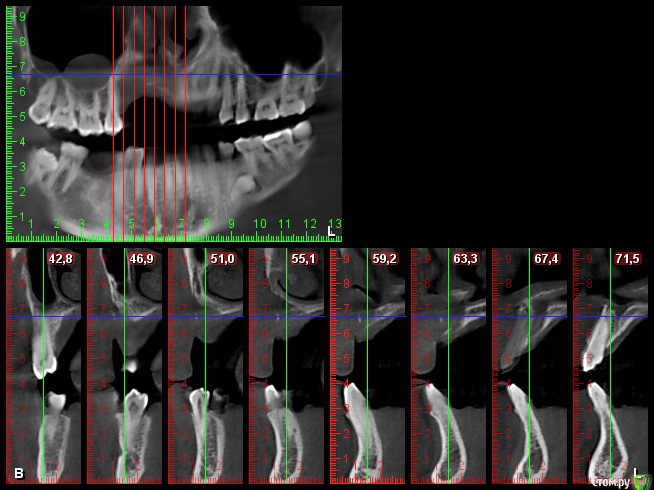

Bier Опубликовано 13 июля, 2017 Поделиться Опубликовано 13 июля, 2017 плохие очень снимки, толком ничего не понятно. Блоки с подвздошки забудьте, они резорбируются быстро. Тут нужен один из вариантов GBR Покажите нормальные срезы, чтобы был ясен уровень костных пиков на соседних зубах. Ссылка на комментарий

L.E.S.I.K. Опубликовано 13 июля, 2017 Автор Поделиться Опубликовано 13 июля, 2017 Возле 21 пик есть, а в обл 25 снижен, корень оголен на четверть. Смущает также отсутствие местами костно дна полости носа Ссылка на комментарий